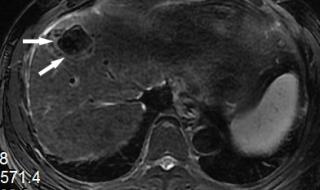

一、原发性肝癌是什么情况原发性肝癌,又叫肝癌,是肝脏细胞或肝内胆管上皮细胞发现的恶性肿瘤。肝脏发现肿瘤,可以是肝脏本身产生的,也可以是其他部位转移而来的。如果比如胃癌转移到肝脏,叫胃癌肝转移。原发性肝癌在我们最常见的是慢性肝炎导致肝硬化,发